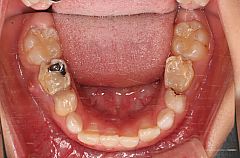

前歯部反対咬合であるものの検査の結果、骨格的な要因の小さな反対咬合でした(前歯の傾きによる反対咬合=歯性の反対咬合)。また、虫歯が非常に多く、上顎左側第二乳臼歯の早期喪失により上顎左側第一大臼歯が手前に移動した結果、上顎左側第二小臼歯の埋伏をきたしていました。

1・リンガルアーチ、セクショナルアーチを装着し、上顎左側第一大臼歯、第一小臼歯間にオープンコイルを装着